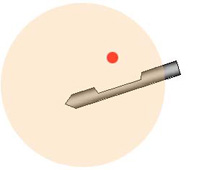

マンモトーム生検の方法

乳房をマンモグラフィで撮影し、位置決めをします。皮下と乳房に局所麻酔をします。これによりほとんど痛みを感じることはありません。病変をマンモグラフィで見ながら、乳房に針を刺入し組織を採取します。

1. 位置決め